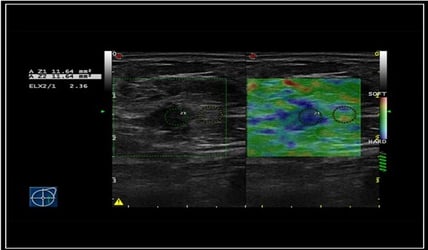

Elastografía avanzada con soporte inteligente

La elastografía se ha convertido en una herramientafundamental en la caracterización mamaria. Nuevos equipos incorporan:

- Elastografía Strain con asistencia en la estabilidad y calidad de la adquisición

- Shear Wave Elastography (2D SWE) con cuantificación objetiva y reproducible

La inteligencia artificial contribuye a:

- Reducir artefactos

- Mejorar la consistencia de las mediciones

- Facilitar el seguimiento evolutivo de lesiones

Esto se traduce en una mejor correlación con los criterios BI-RADS y una mayor seguridad en la toma de decisiones clínicas.